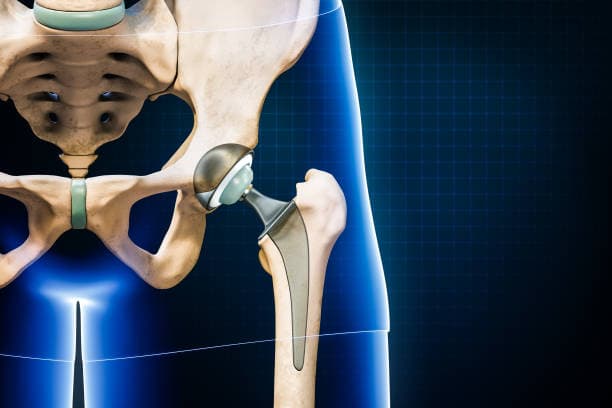

Implant Placement: The prepared bone surfaces are fitted with the prosthetic components. The femoral component, which includes a metal stem and a ball, is inserted into the femur. This can be cemented in place or designed to allow bone growth into the implant. The acetabular component, typically a metal shell with a plastic or ceramic liner, is placed into the prepared socket. These components are aligned to ensure proper joint movement and stability.

The surgical procedure involves making an incision over the hip, through which the surgeon accesses the joint. The damaged femoral head is removed and replaced with a metal or ceramic ball attached to a stem that fits into the femur. The acetabulum is also prepared by removing any damaged cartilage and bone, then resurfaced with a metal or plastic cup. These prosthetic components are designed to mimic the natural anatomy and movement of the hip joint, allowing for smooth articulation and reduced pain.